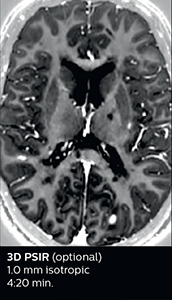

The abbreviated MS protocol for brain is only around 9 minutes, so in case of suspected multiple sclerosis, one or two more advanced sequences may be added, such as PSIR (phase sensitive inversion recovery) or susceptibility-weighted sequences to help us make more confident diagnoses in these inflammatory cases.

In this example, the optional 3D multishot susceptibility weighted sequence with 0.6 mm isotropic voxels is 2 lesions with a central vein sign (arrows) and one lesion with a phase-rim sign (arrowhead). The total scan time, including SmartBrain and axial PD/T2 3mm, is 11:10 min. and is 18:30 min. with the optional 3D PSIR and 3D SWI multishot included.

“In multiple sclerosis patients, we increasingly include a multishot susceptibility sequence [3] in our routine cases, thanks to the shorter scan times. Our abbreviated MS protocol for brain is around 8 to 9 minutes, so we can ask for one or two additional sequences to visualize the central veins, or to get an additional contrast to better depict posterior fossa lesions. In cases of white matter lesions of unknown significance on FLAIR images, for example when we see high signal hyperintensities in the brain, we can add on more advanced sequences such as PSIR (phase sensitive inversion recovery) or susceptibility-weighted sequences to help us in distinguishing between MS and nonspecific or vascular abnormalities in these inflammatory cases.”